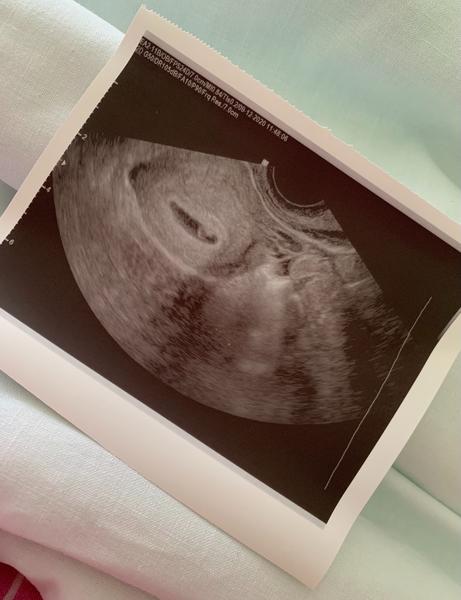

Podlhovastý gestačný vak

Ženy, maminky, prosím vás o radu, resp. upokojenie. Čakáme bábätko, som v 6. týždni. Včera u dr na kontrole bolo vidieť aj bábätko, dokonca aj bijúce srdiečko ❤️. Dr povedal, že všetko vyzerá v poriadku, hoci je ešte malinké. No ja hlúpa, keď sa dnes nad tým zamýšľam, na foto je gest.vak taký podlhovastý, nie okrúhly. No viem, že sa snažil kuknúť na bábo nejak “zboku”, tým, že bolo ešte malilinké, tak možno je to tým? Doktor k tomu nič nepovedal, to len ja som taký analyzátor a všetkého sa bojím. Máte skúsenosť? Prosím upokojte ma, je to vytúžené dieťatko, veľmi dúfam, že všetko bude v poriadku ❤️

podlhovasty gestacny vak je uplne v poriadku 🙂 neviem o tom, ze by mal byt okruhly a tak je to spravne, ani ja som nemala okruhly ani na zaciatku a teraz uz vobec :D

Aj mne to bolo divné najprv... v prvom tehotenstve bol okrúhly a nedopadlo to dobre, tiež som teraz hneď stresovala, ale vserko bude dobre, treba myslieť pozitívne ❤️ Posielam pozitívne myslenie a gratulujem tak isto 🥰

Ahoj, aj ja som take mala tiez cca v 6 tt. Dám ti sem fotku aby si to vedela porovnať keď tak 😊 teraz som už v 22tt a vserko je v poriadku 😊